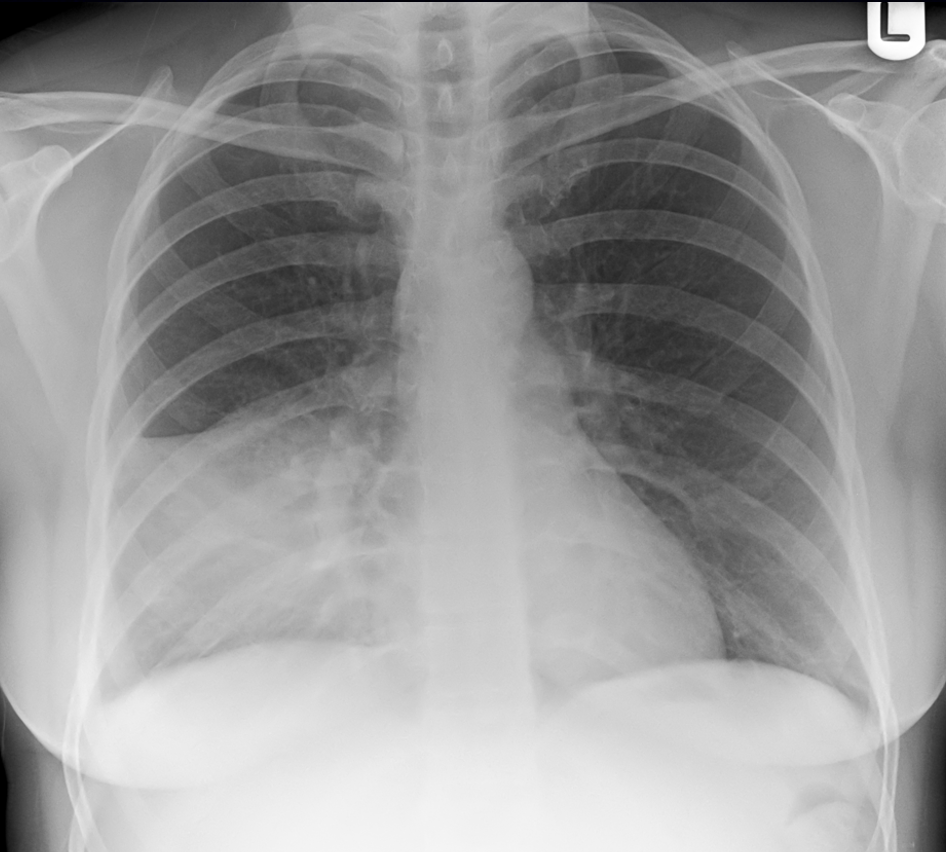

Normal CXR